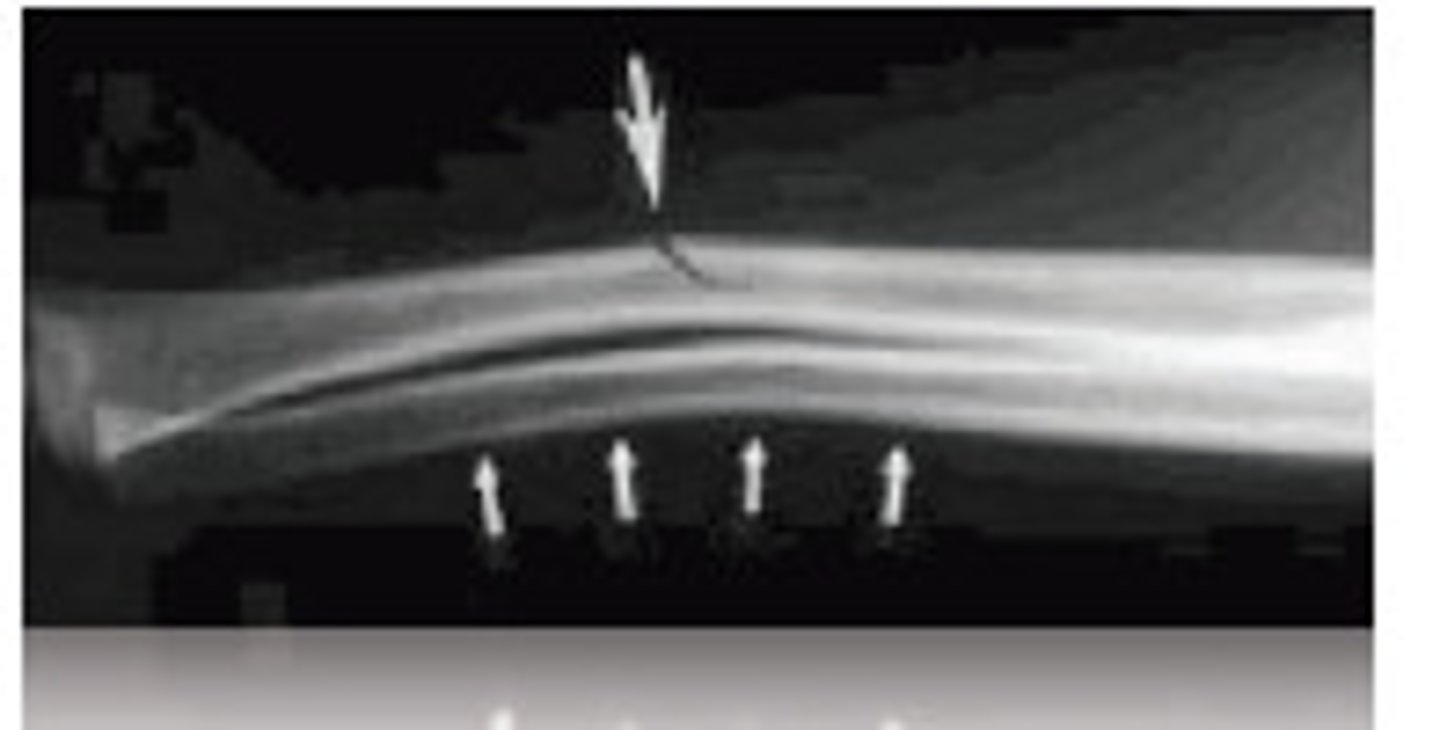

Fracture is nontraumatic in origin, resulted from repeated stress on a bone such as marching or running.

Stress or fatigue fx (march fx)